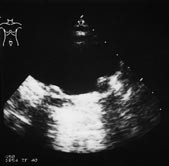

Gjentatt behandling ble utført i 22 refluksuretre, med opphør av refluks i 13, bedring av refluks i seks og uforandret i tre. Hos 13 pasienter, 18 refluksuretre, ble det nødvendig med reimplantasjon. De fleste av disse hadde kompleks refluks. De røntgenologiske funn før og etter behandlingen illustreres i figur 3 der miksjonscystografi tre måneder etter behandlingen viser at refluksen er forsvunnet på begge sider. Ved ultralydundersøkelse av blæren kan teflonpasta sees som ekkorike, skyggegivende små oppfyllinger ved ostiene (fig 4).